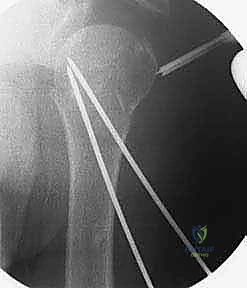

4. إدخال الأسلاك المعدنية (K-wires)

بمجرد أن يصبح الكسر في الوضع المثالي، يتم إدخال أسلاك كيرشنر (Kirschner wires) الدقيقة عبر الجلد مباشرة إلى العظم. يتم توجيه هذه الأسلاك بزوايا هندسية مدروسة لضمان أقصى درجات الثبات. عادة ما يتم استخدام 2 إلى 4 أسلاك.

5. التحقق من الثبات وقص الأسلاك

بعد وضع الأسلاك، يتم تحريك الكتف بحذر للتأكد من ثبات الكسر التام. بعد ذلك، تُقص نهايات الأسلاك وتُترك بارزة قليلاً فوق الجلد (أو تُدفن تحت الجلد مباشرة) لتسهيل إزالتها لاحقاً.

6. التقييم النهائي والإغلاق

تُؤخذ صور شعاعية نهائية لتوثيق نجاح العملية، وتُغطى مواقع دخول الأسلاك بضمادات معقمة.

صور إضافية من داخل غرفة العمليات توضح دقة الإجراء: